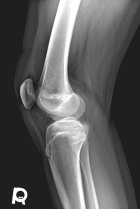

14 year old female with a tender right knee mass which has been enlarging for five months